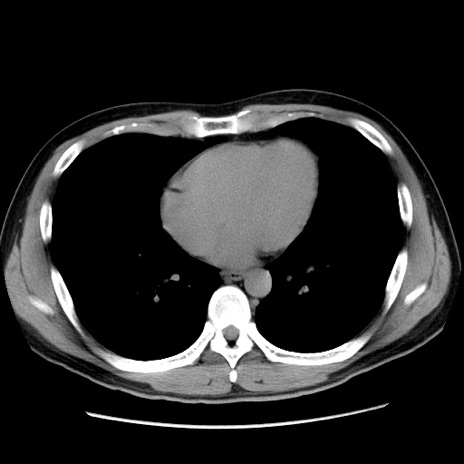

冠状断像

症例36(横断像)

【症例】20歳代 男性

【主訴】心窩部痛

【現病歴】今朝より上腹部痛あり。一旦軽快していたが再度出現したため救急要請。昨日夕に白身の魚を含む刺身を食べた。

【身体所見】BP 136/89mmHg、HR 74/min、BT 37.0℃、腹部:膨満、軟、心窩部に圧痛あり。反跳痛なし、筋性防御なし、腸雑音やや亢進あり。

【データ】WBC 17700、CRP 0.48